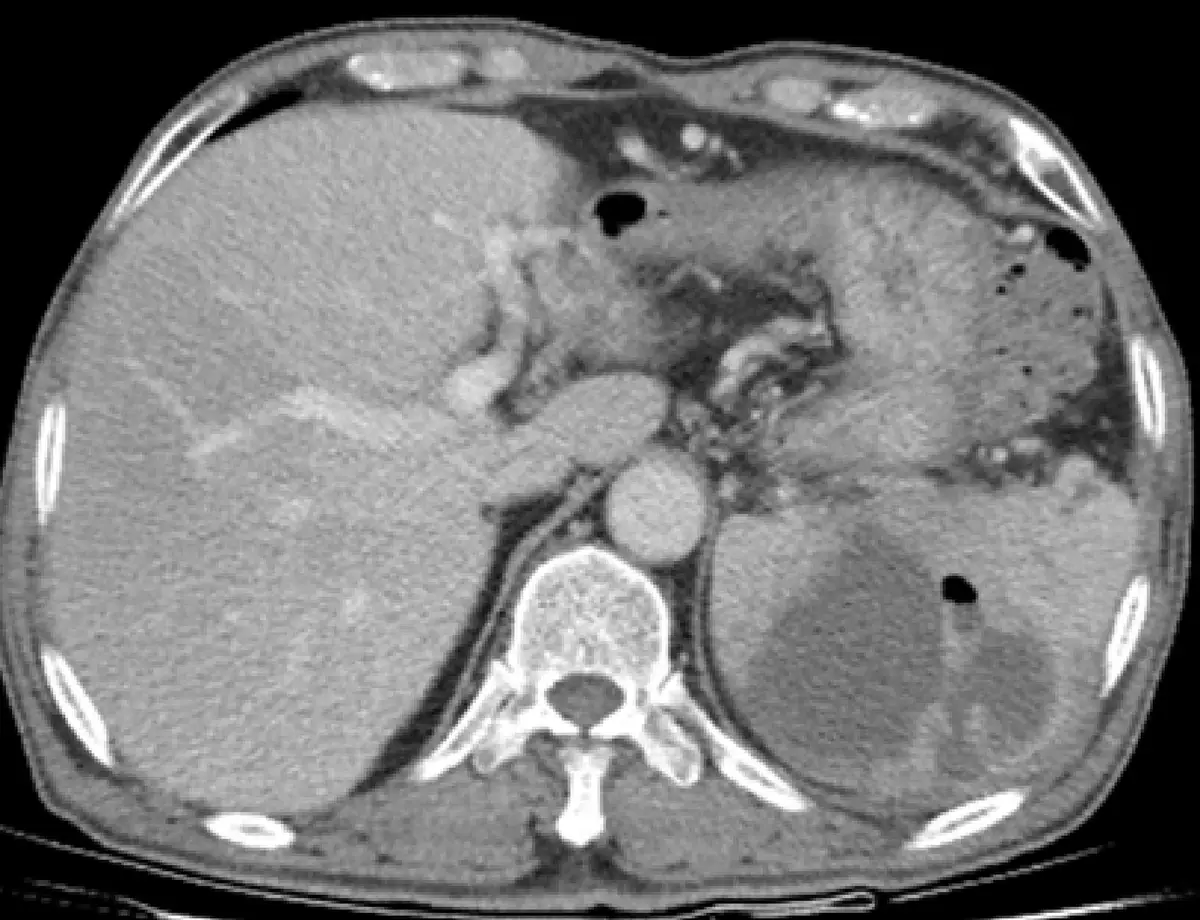

本圖為腹部軸向對比增強電腦斷層(axial contrast-enhanced CT)影像,可觀察到以下特徵:

- 脾臟病灶:位於畫面左側的脾臟內,可見一大型不規則低密度(hypodense)病灶,邊緣具有對比增強的環形強化(rim enhancement),中央呈液體密度,符合膿瘍的典型 CT 表現。

- 氣體訊號:病灶內/旁可見數個極低密度的小氣泡影(gas bubbles),此為化膿性膿瘍的特徵性表現,出現氣體本身即為膿瘍的診斷依據(pathognomonic finding)。

- 周邊脂肪層:脾臟周圍脂肪層模糊、密度稍增加,顯示局部發炎反應向被膜外蔓延。

- 其他結構:肝臟(右側)密度均勻,無明顯異常;主動脈及下腔靜脈可見;脊椎及兩側腰大肌影像完整,無獨立腰大肌膿瘍徵象。

結論:CT 所見之脾臟內低密度含氣集液病灶伴周邊環形強化,高度符合脾臟膿瘍(splenic abscess)的診斷。